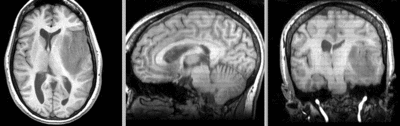

• Phase 1: BRAINSfit rigid w/o masking

1. open the Registration / BRAINSfit module

1. Select Preset "Xf0_Rigid" or set the parameters as shown below:

2. fixed image: SPGR; moving image: fMRI

3. Registration phases:

1. Initialize check: useGeometryAlign; check: Rigid

4. Output: under Slicer Linear Transform, select "create new" and rename to "Xf0_Rigid" or similar

5. leave rest at defaults

6. click: Apply

after rigid registration after rigid registration